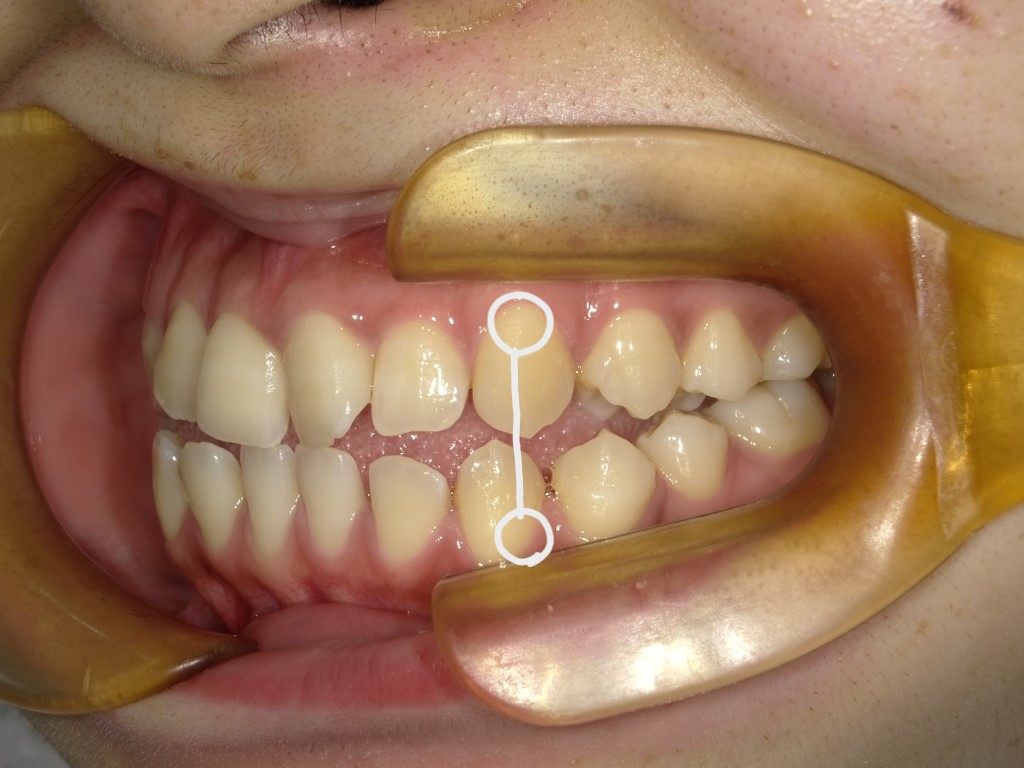

舌癖がある方の治療症例

最後に症例のご紹介をします。

患者様のご協力次第では治療期間も変わってきます。舌の位置の見直しをしましょう!!